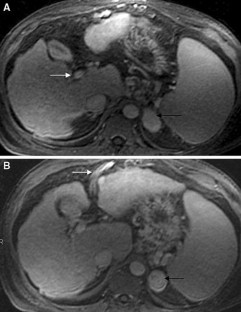

Fig. 1.

Fig. 2.

Fig. 3.

Fig. 4.